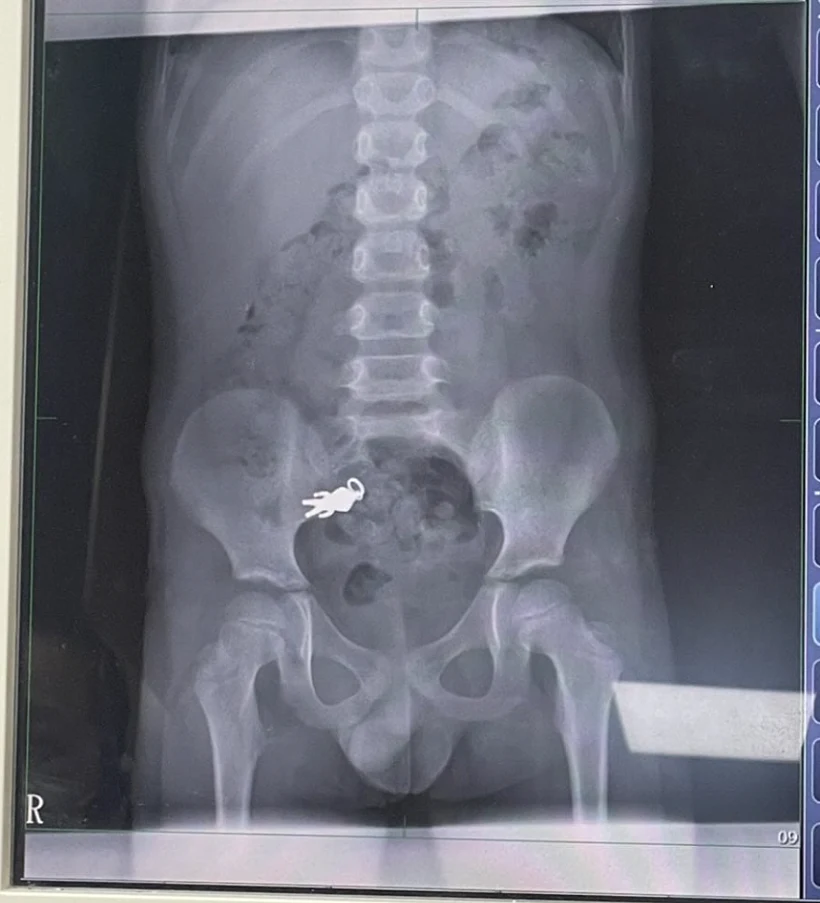

הרופאים בבית החולים לואודונג בו-אי ערכו צילום רנטגן וגילו כי החפץ נתקע במעיים. ד"ר שיאה צ'ינטונג, שטיפל בילד, סבר כי מאחר ולא הופיעו סימנים של כאבים חריפים או חסימה, לא היה צורך בניתוח. הוא המליץ למשפחה להמשיך במעקב בבית, והזהיר כי הופעת כאבים חזקים, הקאות או עצירות ממושכת תחייב טיפול מיידי.

הצילום בו נראה מחזיק המפתחות בבירור, פורסם על ידי בני המשפחה ברשתות החברתיות ועורר תגובות רבות. גולשים רבים הגיבו בהומו על "מסע הגיבור" בתוך גופו של הילד. אחרים הביעו ביקורת כלפי ההורים על שלא השגיחו על ילדם.